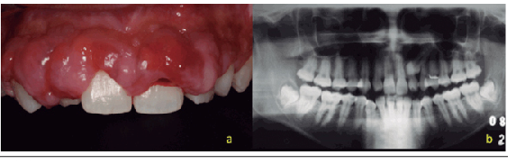

Clinical examination presents a lobulated aspect of the gingiva with severe gingival enlargement with clinical crowns covered to a large extent, showing a bucco-lingual dimension greater than 3 mm and a depth of probing greater than 6 mm (Figure 1). On palpation the gingiva was firm and resilient in consistency. Clinically, the patient still had a visible plaque and visible areas of gingival bleeding (Figure 2a). In the radiographic examination there were no horizontal bone resorptions, either localized or generalized (Figure 2b).